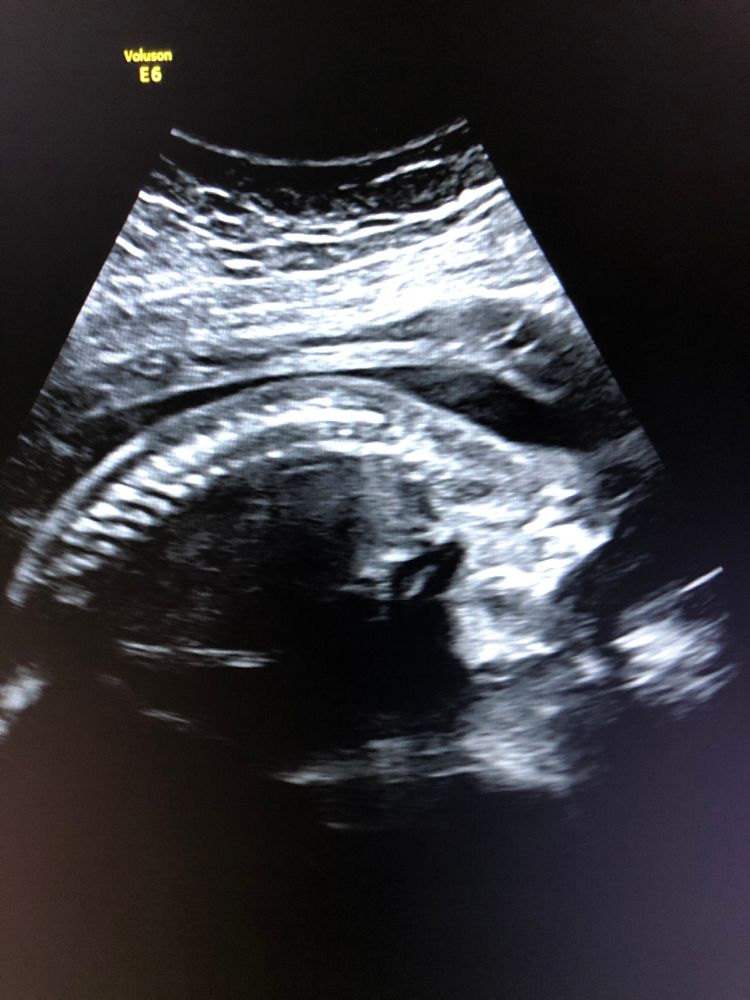

ниже прикреплю снимки абсолютно «нормальных» спинок😌 специально сохранила примерно в таком же положении как у Вас

по поводу - где право/лево и верх/низ - по снимку сказать нельзя, так как все зависит от положения датчика при осмотре😊 тем более человек во время осмотра был в поперечном положении. Обычно в левой стороне экрана - либо право либо верх😀 но это совсем необязательно.

на вашем снимке получается, что голова находится справа (в животике слева - если датчик был расположен «стандартно»). И человек смотрит вниз - поэтому мы видим затылок